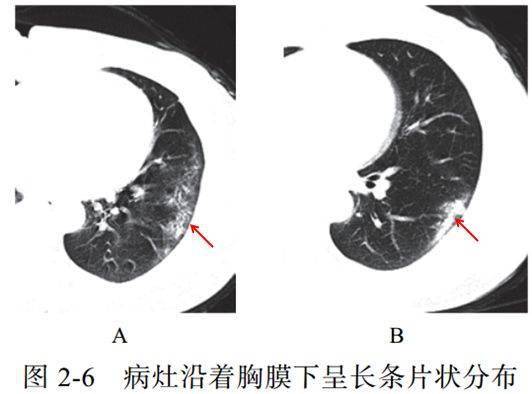

(六)长轴与胸膜平行

病灶沿着胸膜下呈长条片状分布,一般不引起胸膜反应

提示病理改变:病变首先累及皮层肺组织,不按肺段解剖分布,对细菌性肺炎病灶分布有一定的鉴别意义(图 2-6)